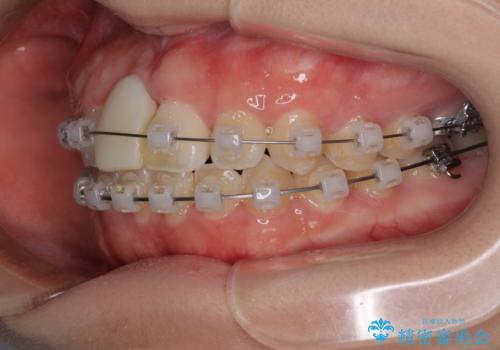

- 矯正装置

- クリアブラケット

ぶつけてしまった歯は保存が困難な状況であったので抜歯をし、ワイヤー矯正により歯列を整えつつ前歯の突出感を解消することとしました。

矯正治療後にはインプラント補綴治療を行うこととしました。